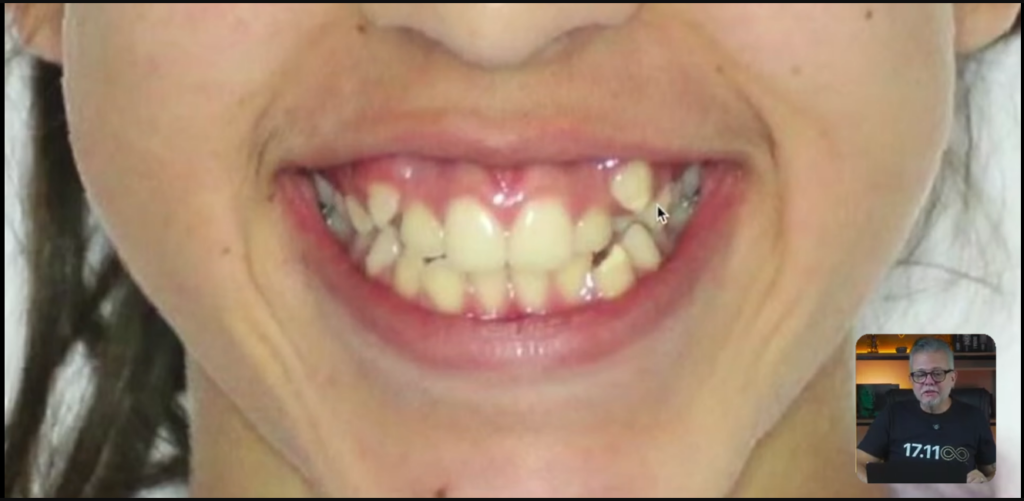

O diagnóstico dessa paciente aqui é uma paciente dólico-facial. Ela tem um sorriso gengivoso que não tem conserto sem cirurgia ortognática.

Hélio, como é que você sabe que esse sorriso gengivoso não tem conserto sem a cirurgia ortognática?

Eu sei que não dá para consertar, justamente porque ela nem tem uma mordida profunda que me permite intruir os incisivos superiores.

Se eu pudesse intruir os incisivos superiores, provavelmente eu ia melhorar esse sorriso gengivoso.

Mas ela não tem mordida profunda.

Então, eu já vou dizer para essa paciente o seguinte:

olha, eu vou melhorar muito o seu sorriso, mas eu não consigo corrigir o sorriso gengivoso. Ponto.

A não ser que você queira fazer uma cirurgia ortognática.

E, nesse momento, como não era uma coisa que incomodava demais ela, ela falou assim:

não, não, vamos deixar isso para uma próxima, tá tudo bem.

Então, a paciente dólico, você pode observar na face dela, ela não tem grandes assimetrias.

Então, essa nossa paciente, ela tem todo esse apinhamento.

Vocês estão vendo que ela está de classe 1, do lado direito e do lado esquerdo?